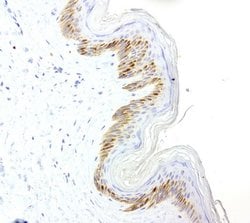

VSNL1 Mouse anti-Human, Clone: UMAB115, lyophilized, UltraMAB™

This gene is a member of the visinin/recoverin subfamily of neuronal calcium sensor proteins. The encoded protein is strongly expressed in granule cells of the cerebellum where it associates with membranes in a calcium-dependent manner and modulates intracellular signaling pathways of the central nervous system by directly or indirectly regulating the activity of adenylyl cyclase. Alternatively spliced transcript variants have been observed, but their full-length nature has not been determined.

Immunohistochemistry (Paraffin)

Human recombit protein fragment corresponding to amino acids 2-191 of human VSNL1 produced in E.coli.